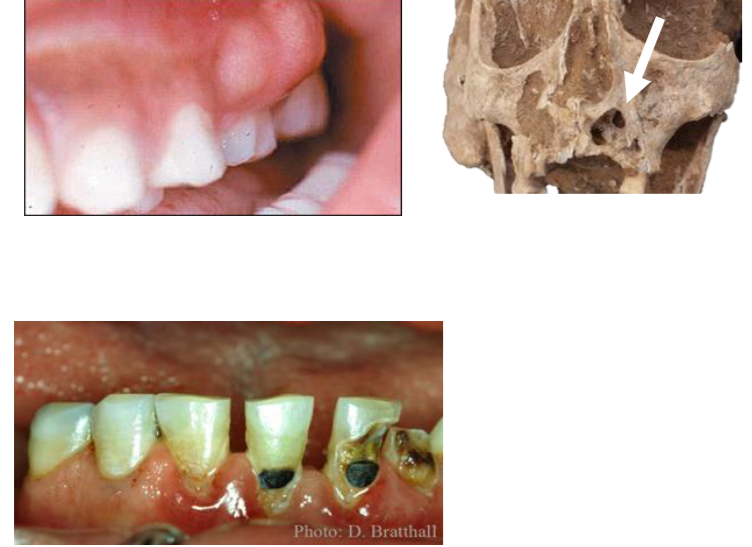

Pathology: Inflammatory or Infectious Disease Example: Dental abcesses & caries

Abscesses form when food particles get stuck between teeth and bacteria festers

Dental caries (=cavities) form from acid-producing bacteria

Pathology: Metabolic Diseases Example: Cribra orbitalia and Porotic hyperostosis

Porosity of superior orbit or cranial vault

Nonspecific indicator of stress

Malnutrition, illness, anemia